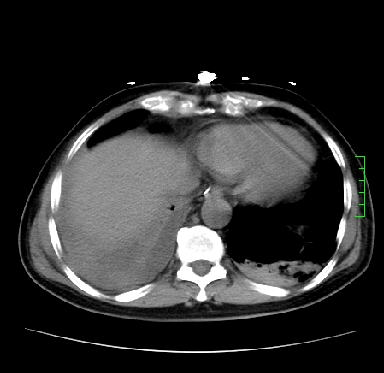

icu病人,几天都没明确诊断。m,76y,咳嗽、咳痰1周,伴气促,右胸痛入院,pe:t38.3c p135 r25 bp135/85。双肺可闻及大量湿罗音,心、腹未见明显异常。诊断:1心衰?2肺部感染?3冠心病?

11号ct

双肺感染性病变,下叶膨胀不全,胸水,左室大。

1)两肺感染性病变(右肺下叶肺脓肿可能)。2)双侧胸腔积液,以右侧为甚。

混合型肺水肿合并感染,肺膨胀不全,胸膜肥厚粘连包裹,同时肺内有陈旧性病灶。注意复查

ards,肺感染性病变,右下叶实变,双侧胸腔积液,右侧为著,叶间胸膜积液,右上肺陈旧性tb纤维灶,左室大。

考虑双肺感染、右肺下叶肺脓肿伴双侧胸腔积液,肺水肿。

考虑:双肺感染、右肺下叶肺脓肿,双侧胸腔积液,肺水肿.请结合临床.